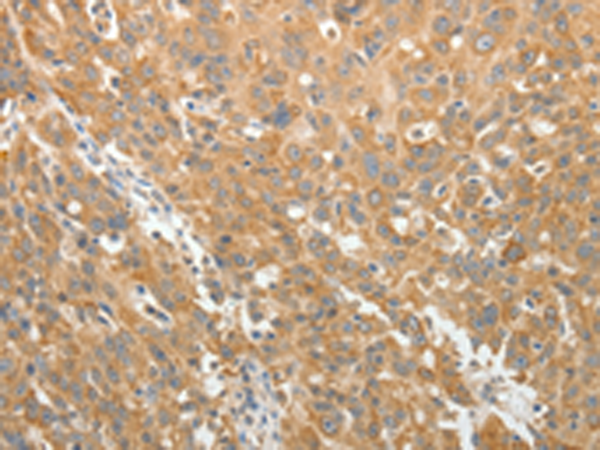

分类: 科研抗体货号: P11198别名: ARC20; P20-ARC应用: WB,IHC反应种属: Human, Mouse